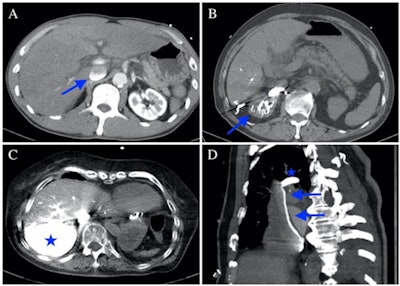

The CAP sign shows the effect of gravity, the group explained.

"The density of contrast agent is much higher than that of blood; thus, during normal physiological blood flow, specific gravity has little effect on the contrast agent dynamics," the team wrote. "In patients with cardiogenic shock or impending circulatory collapse, both the arterial and venous blood flow dramatically decreases, and the contrast agent tends to accumulate in the dependent parts of the venous system."